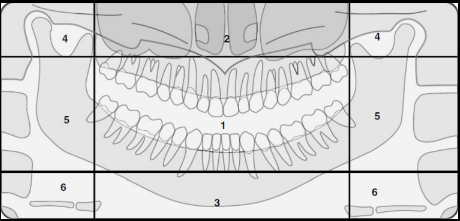

Identify The Zones.

Zone 1: Dentition

Zone 2: Nasal Cavity and Maxillary Sinuses

Zone 3: The Mandible

Zone 4: Temporomandibular Joints (TMJs)

Zone 5: Spine and Ramus

Zone 6: Hyoid Bone